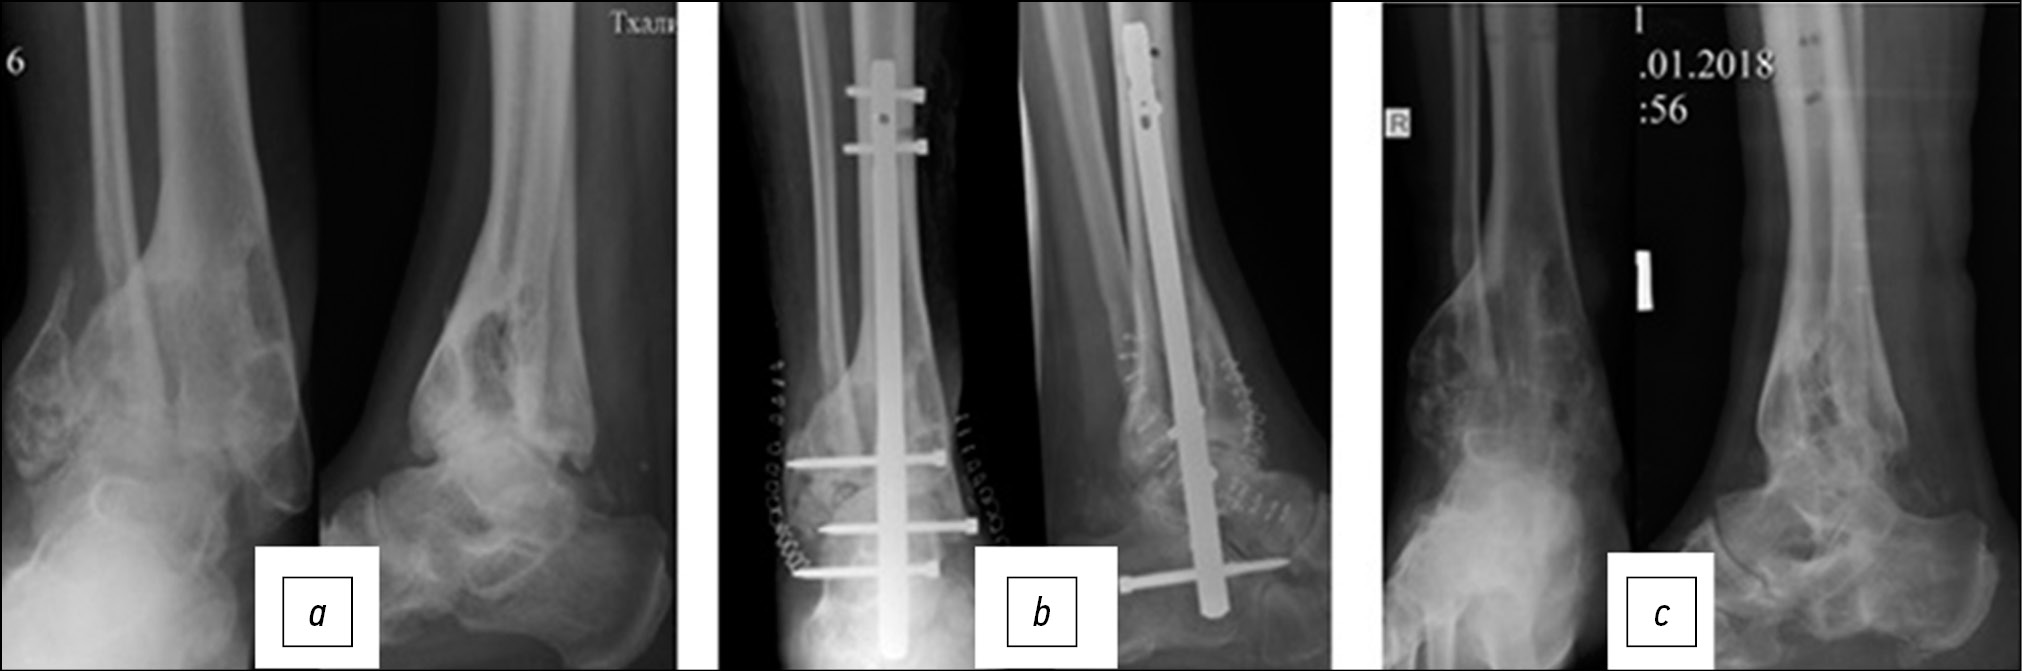

Пациент Т., 40 лет, обратился в НИИТОН СГМУ через 10 мес после получения травмы. По результатам проведенного обследования установлен диагноз: неправильно сросшиеся переломы дистального отдела правой БК и МК, комбинированная деформация голени; посттравматический правосторонний крузартроз 4 стадии; контрактура правого ГС; болевой синдром (рисунок, а).

Оперативное вмешательство выполнено под спинномозговой анестезией с наложением пневматического жгута в нижней трети бедра. Доступ по наружной поверхности дистального отдела голени, после отведения наружной лодыжки выполнена артротомия и артролиз ГС. Для устранения деформации произведена моделирующая клиновидная резекция суставной поверхности БК и экономная моделирующая резекция ТК. После фиксации ГС интрамедуллярным ретроградным стержнем и его блокирования свободную часть дистального отдела МК фрагментировали и переместили в область дефекта БК по наружной поверхности (рисунок, б).

Послеоперационный период протекал без осложнений. Через 10 нед. после операции пациент передвигался с полной опорой на конечность, и вернулся к прежней трудовой деятельности. Костный анкилоз ГС был отмечен при контрольной рентгенографии через 12 мес после оперативного вмешательства. В этот период больной предъявлял жалобы на периодические боли в проекции установленных металлоконструкций, в связи чем выполнено их удаление через 14 мес после первичного оперативного вмешательства (рисунок, b).

Рисунок. Рентгенография голеностопного сустава больного Т., 40 лет (а) на момент обращения, (b) после выполнения операции, (c) через 14 мес после операции, интрамедуллярный фиксатор удален

Figure. X-ray image of 40 y. o. patient T’s ankle joint (a) at presentation, (b) after the surgery, (c) in 14 months after the surgery, intramedullary fixator removed

Индивидуальные показатели FFI на момент удаления металлоконструкции составили 31,5 балл.